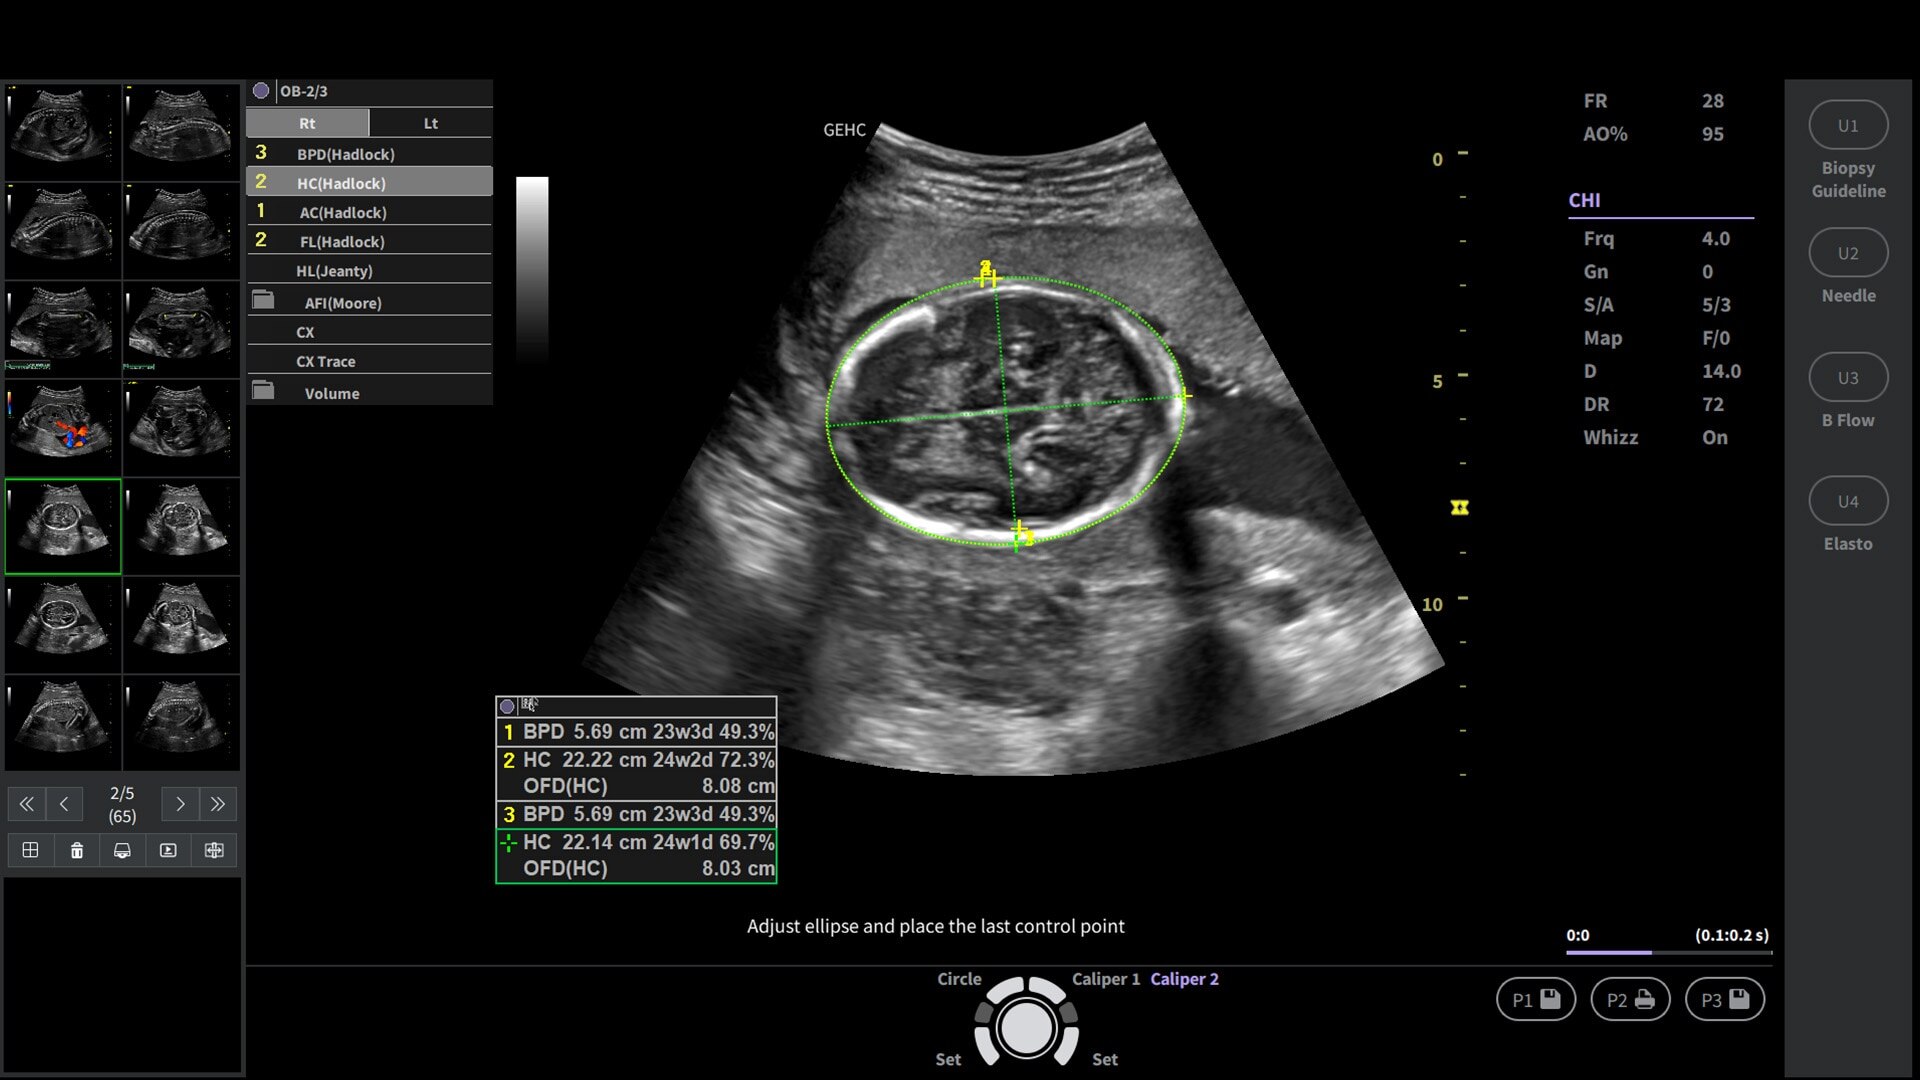

Powered by VisionBoost Architecture, Versana Premier provides optimal image quality so users can easily reach a diagnosis. Advanced clinical features help address challenging cases while automated tools help reduce scan time:

• Make automated 2D Measurements and Volume Calculations with Auto Contour, Auto Bladder, Whizz Follicle and Auto-IMT

Support OB scanning with faster 3D/4D rendering and capture incredible static 3D/4D imaging